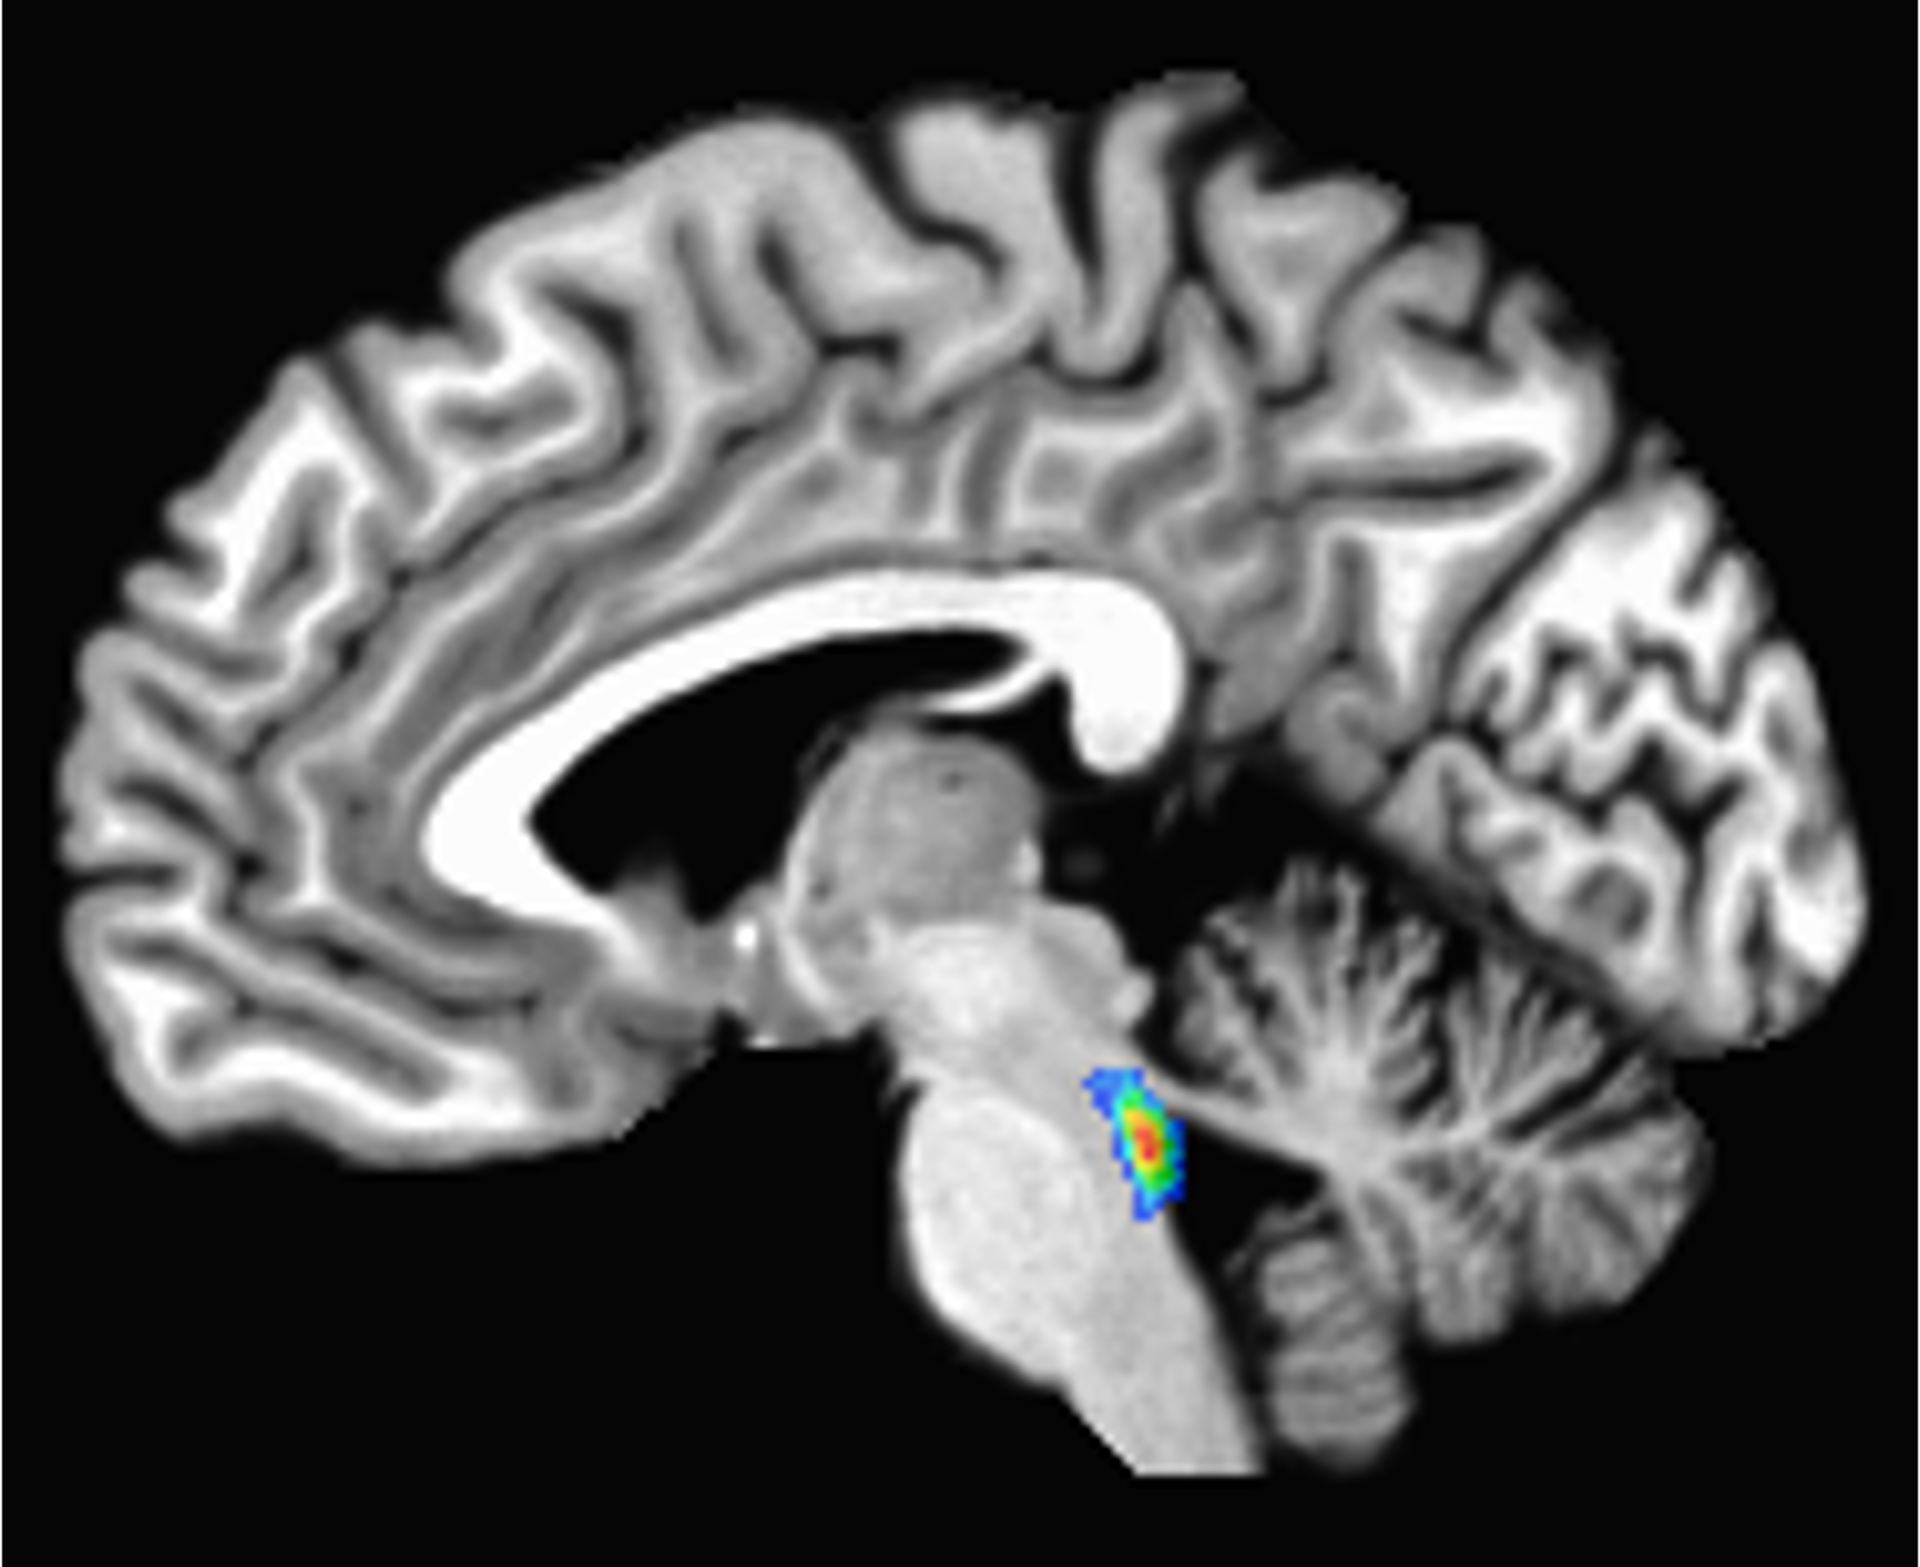

In the earliest of these changes, a tangled version of a protein called tau starts building up in a tiny region deep in the brain involved in sleep, attention and alertness, called the locus coeruleus. Tau later spreads to the rest of the brain.

The locus coeruleus sits in the brain stem, the lowest part of the brain. Its name, “blue spot,” comes from a pigment called neuromelanin that its cells produce.

Studies suggest that starting in middle age, nerve cells in the locus coeruleus may get damaged by tau buildup, and that damage may correlate with declines in memory. Tau buildup, cell death and loss of function in the locus coeruleus precedes and predicts Alzheimer’s diagnosis and symptoms.